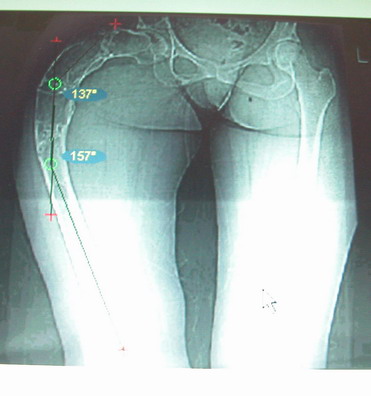

Моё мнение, что двойная остеотомия бедра с аппаратом Илизарова + Гексаподный механизм, или Тэйлора, В данной ситуации является методом выбора. Я очень извеняюсь за качество прилагаемых снимков, в которых я постарался отразить разницу междe одной и двумя остеотомиями бедра.

Собственно сустав не беспокоит, объем движений полный. По скиаграммам получается, что достаточно одной остеотомии на вершине деформации, чтобы восстановить длину и вывести коленный сустав в нужное положение.

Т.к. укорочение 7 см, то начинать будем с соеотомии и коррекции аппаратом. Спасибо